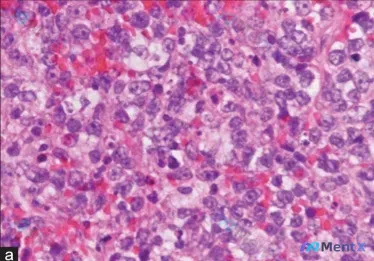

整理了一个很有启发的病理读片思路,这个病例的形态学组合挺容易踩坑的,分享给大家。 先看病例核心形态学表现 - 背景:淋巴组织结构破坏 - 肿瘤细胞:弥漫性增生的异型肿瘤细胞,体积大,多形性明显 - 细胞形态:梭形 + 多边形混合,部分可见多核巨细胞 - 核特征:核大深染,核内不规则假包涵体,多个核仁...

今天看到一张很有警示意义的HE染色病理片,整理一下完整的分析思路,和大家一起讨论。 先看镜下核心表现 - 染色与结构:标准HE染色,核呈深蓝色/紫黑色,胞浆粉红色;完全看不到正常的腺管、小叶或鳞状上皮结构,细胞呈实性、弥漫性片状铺展,边界不清,黏附性低。 - 细胞异型性:核普遍增大、大小不等、多形性...